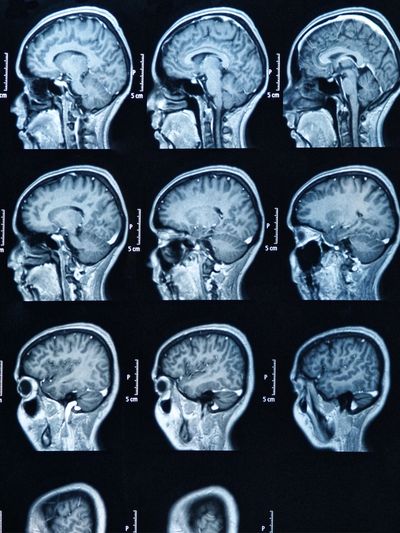

Diagnosing Chiari malformation involves a combination of medical history evaluation, neurological examination, and imaging studies. The diagnostic process aims to assess the structure of the brain, the presence of herniation, and any associated abnormalities. The steps for diagnosing Chiari malformation typically include:

Imaging Studies:

Once a diagnosis of Chiari malformation is confirmed, the medical team, which may include neurologists, neurosurgeons, and neuroradiologists, will determine the most appropriate course of treatment. Treatment options may include observation, medications to manage symptoms, or surgery to alleviate pressure on the brain and spinal cord caused by the herniation.